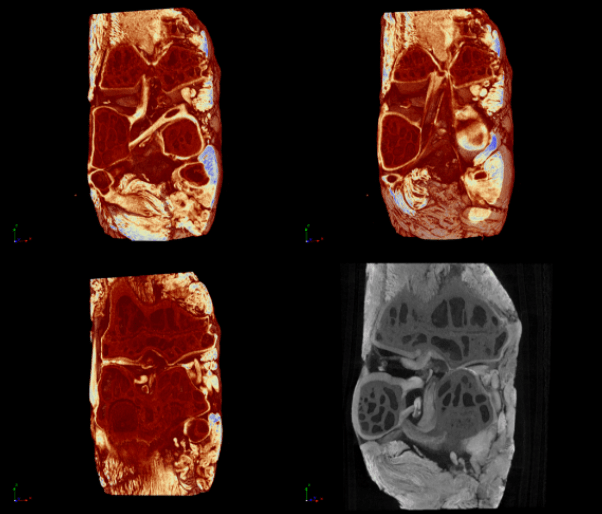

Cartilage analysis

Through the use of contrast agents to enhance the visibility of specific tissues (example, phosphotungstic acid – PTA or Lugol’s iodine), along with SkyScan Micro-CTs highly sensitive detectors, cartilage can be resolved in 3D. This broad range of applications makes the Bruker micro-CT products a perfect choice for core facilities allowing numerous users to benefit from a single system.